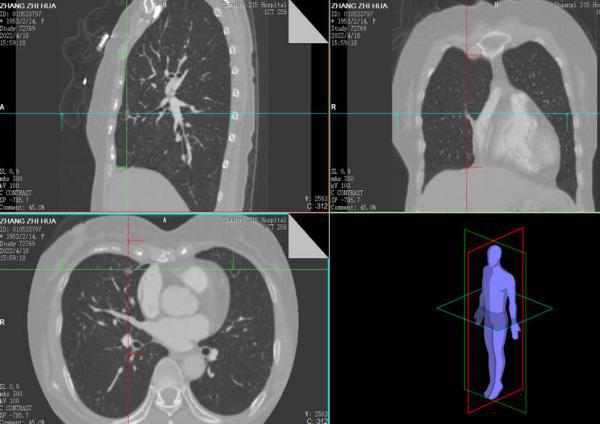

肺段切除术是肺结节及早期肺癌的重要治疗手段之一,精准的肺段手术是肿瘤学疗效和肺功能保护的前提,目标是在彻底切除病灶的同时最大程度地保留健康肺组织。胸外科团队通过专业软件对肺结节的位置进行了精确的定位,清晰显示出结节所处的肺段及靶段相关的支气管、血管情况。根据信息在术前进行详细的手术规划,确保了术中安全的、精准的切除靶肺段。